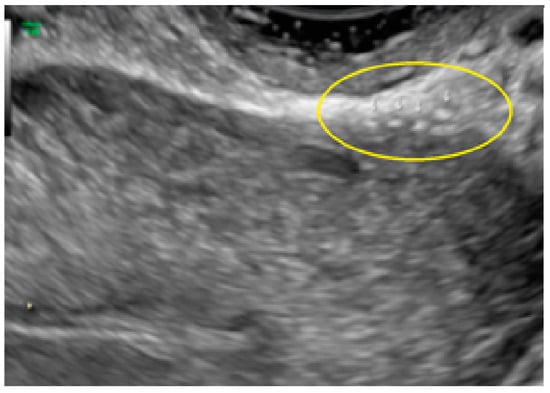

- The presence of hypoechogenic associated tissue (hypoechoic areas surrounding a small cyst area; we called this a “hat”). This tissue does not protrude or invaginate the peritoneal surface.